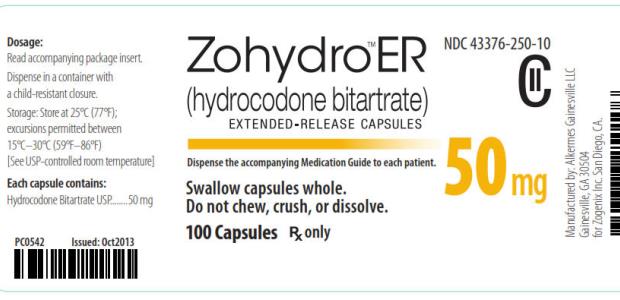

Dr. Margaret A. Hamburg writes that the states "have an important role to play in addressing a critical driver of opioid abuse -- inappropriate prescribing practices. However, we can't just focus on one drug, Zohydro, alone."